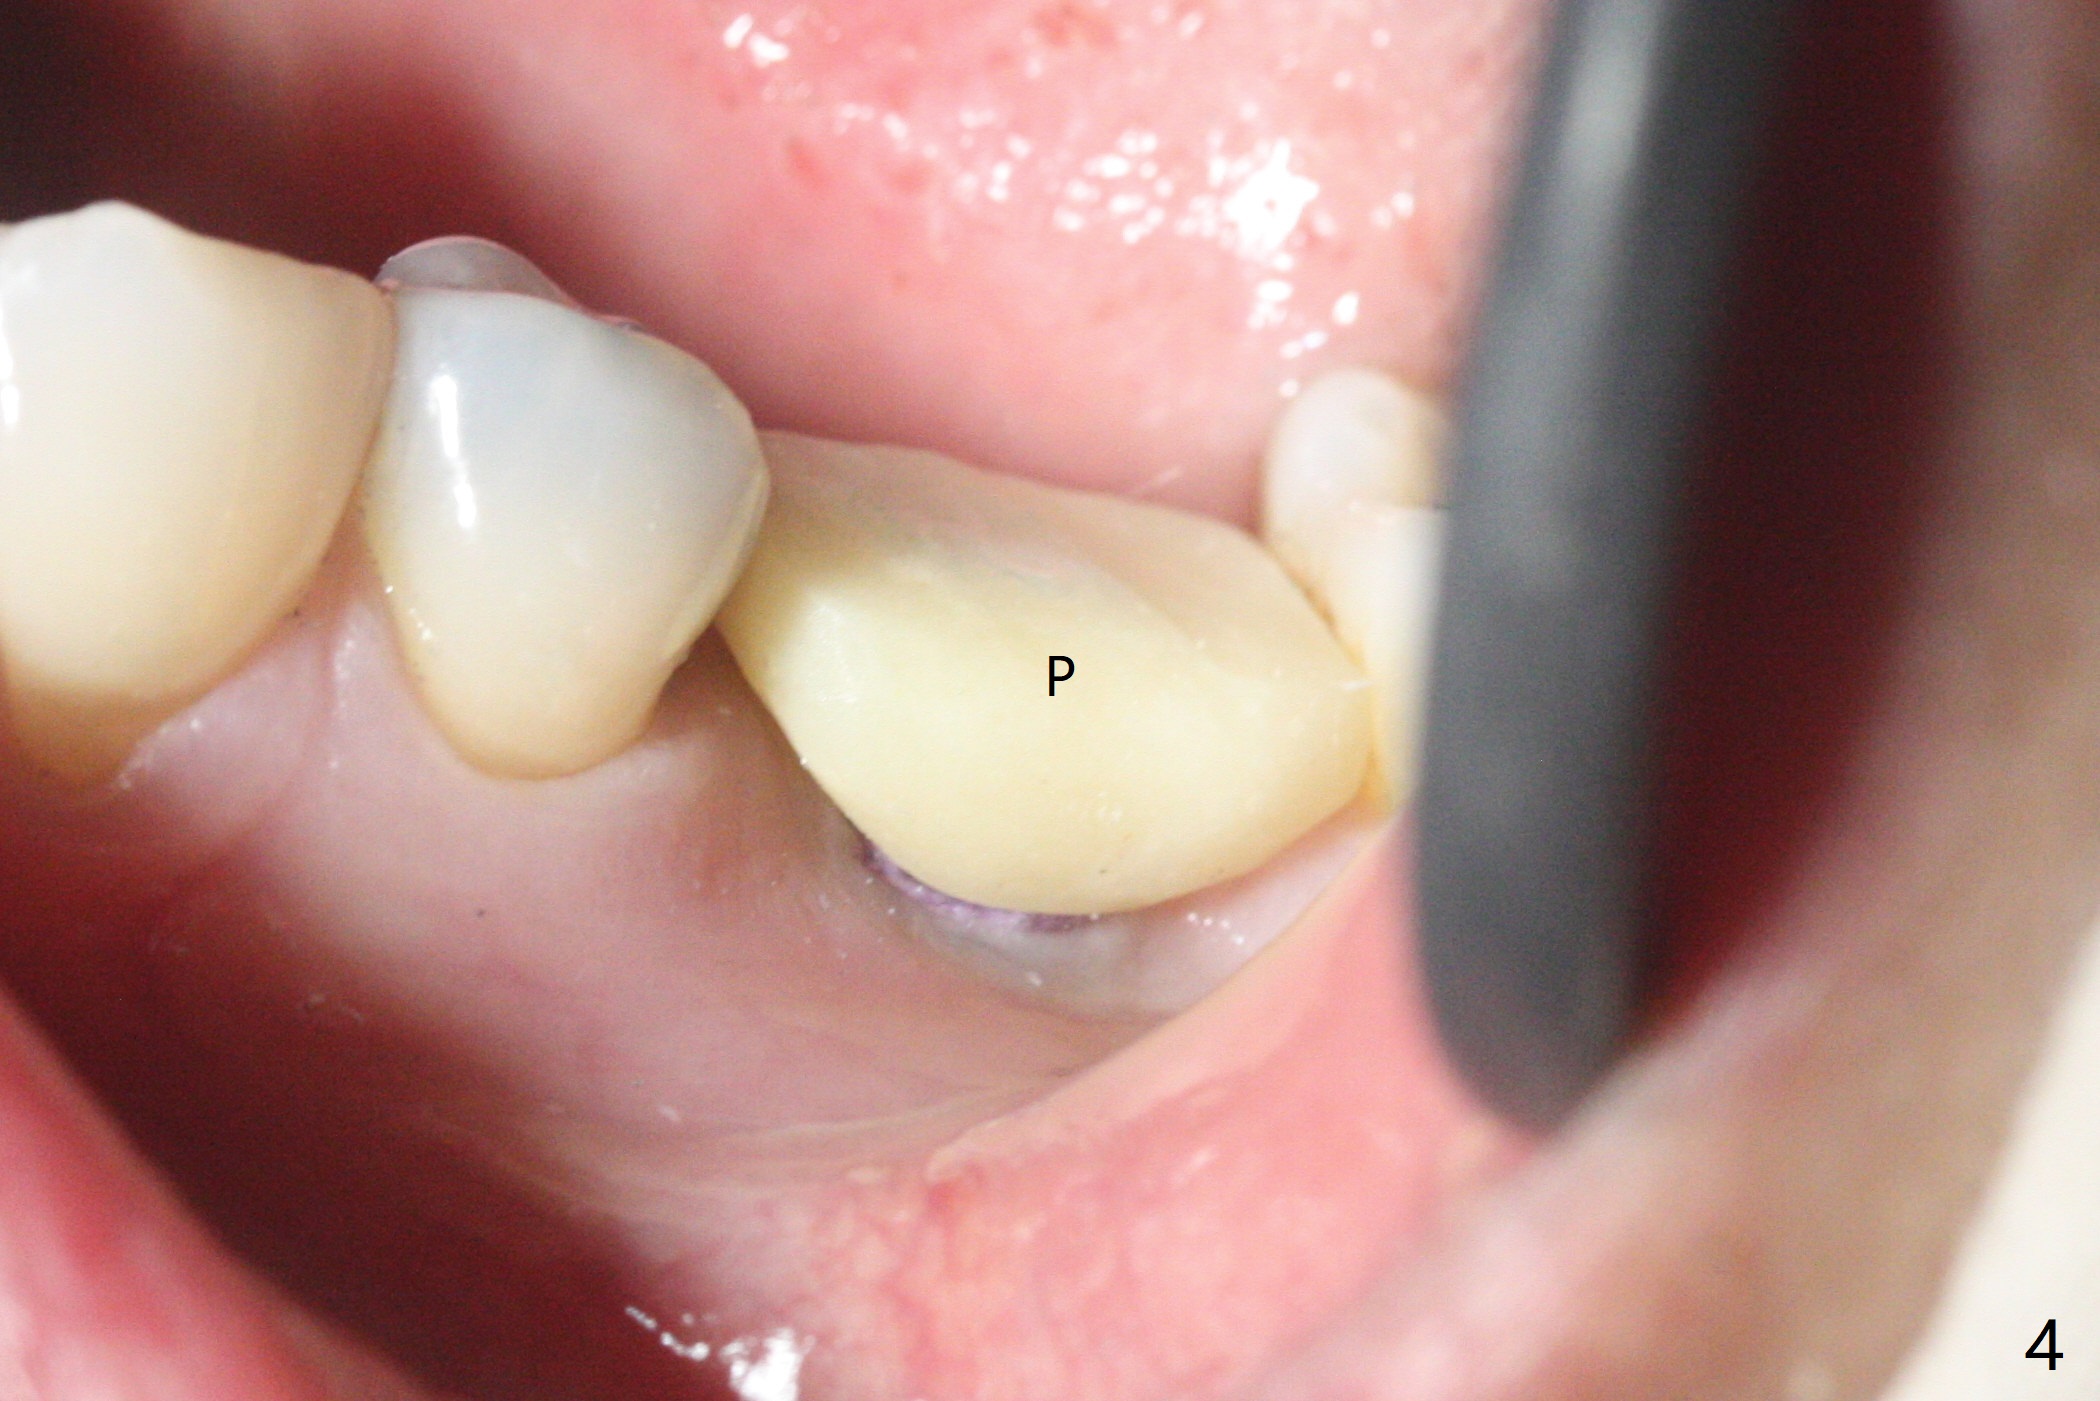

适当更改导板(为两段式接近圆柱状植体设计)钻洞顺序(根尖钻头小,而一段式植体根尖特别尖),5x14毫米一段式软组织水平植体植入,扭力大约35Ncm(图一),略微种深(图二:长箭头)后,磨短基台(与图一对比;左上6伸长),颊侧,远中,舌侧边缘降低(图二,三:<;增加基台高度,提高牙冠固位),制作临时牙冠(图四:P),主要目的将近中牙龈推向近中(图三:空箭头),暴露近中基台边缘,以后好取模。总之,一段式植体需要考虑临时修复。术后两个月临时牙冠和周围牙龈正常(图五)。术后4.5月轻度骨质吸收(图六),临床上看不出来螺纹将要暴露,取模。病人抱怨用临时牙冠咀嚼疼痛,不咬后没有不舒服,其实临时牙冠咬合面穿孔,牙龈正常,永久粘固剂没有外溢(图七)。术后4.5-6个月植体周围骨质吸收(图六,七)。牙槽嵴处钻洞应与植体直径一样才能减少骨质吸收。